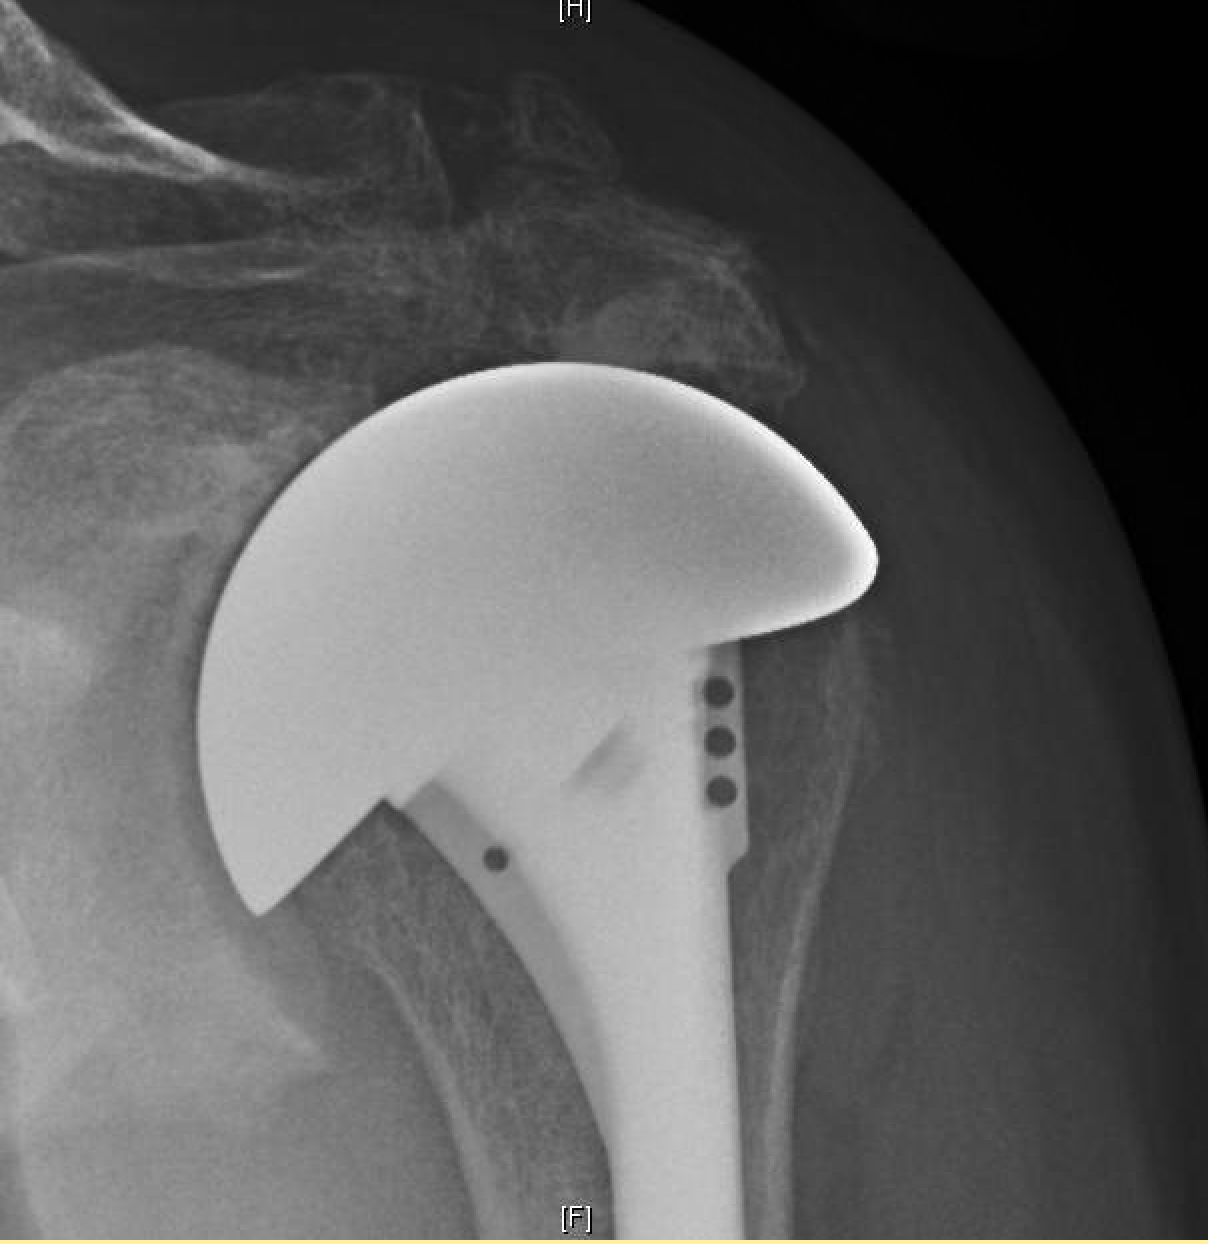

Reverse Total Shoulder Arthroplasty for Rotator Cuff Arthropathy Musculoskeletal Key Shoulder X Ray Torn Rotator Cuff Standard views should include a true. If the physical exam suggests you may have a torn rotator cuff, your doctor may order magnetic resonance imaging (mri), a. A rotator cuff tear is a common injury affecting the shoulder, involving a tear in one or more of the tendons that comprise the rotator. An injury to the rotator cuff, such as. Shoulder X Ray Torn Rotator Cuff.